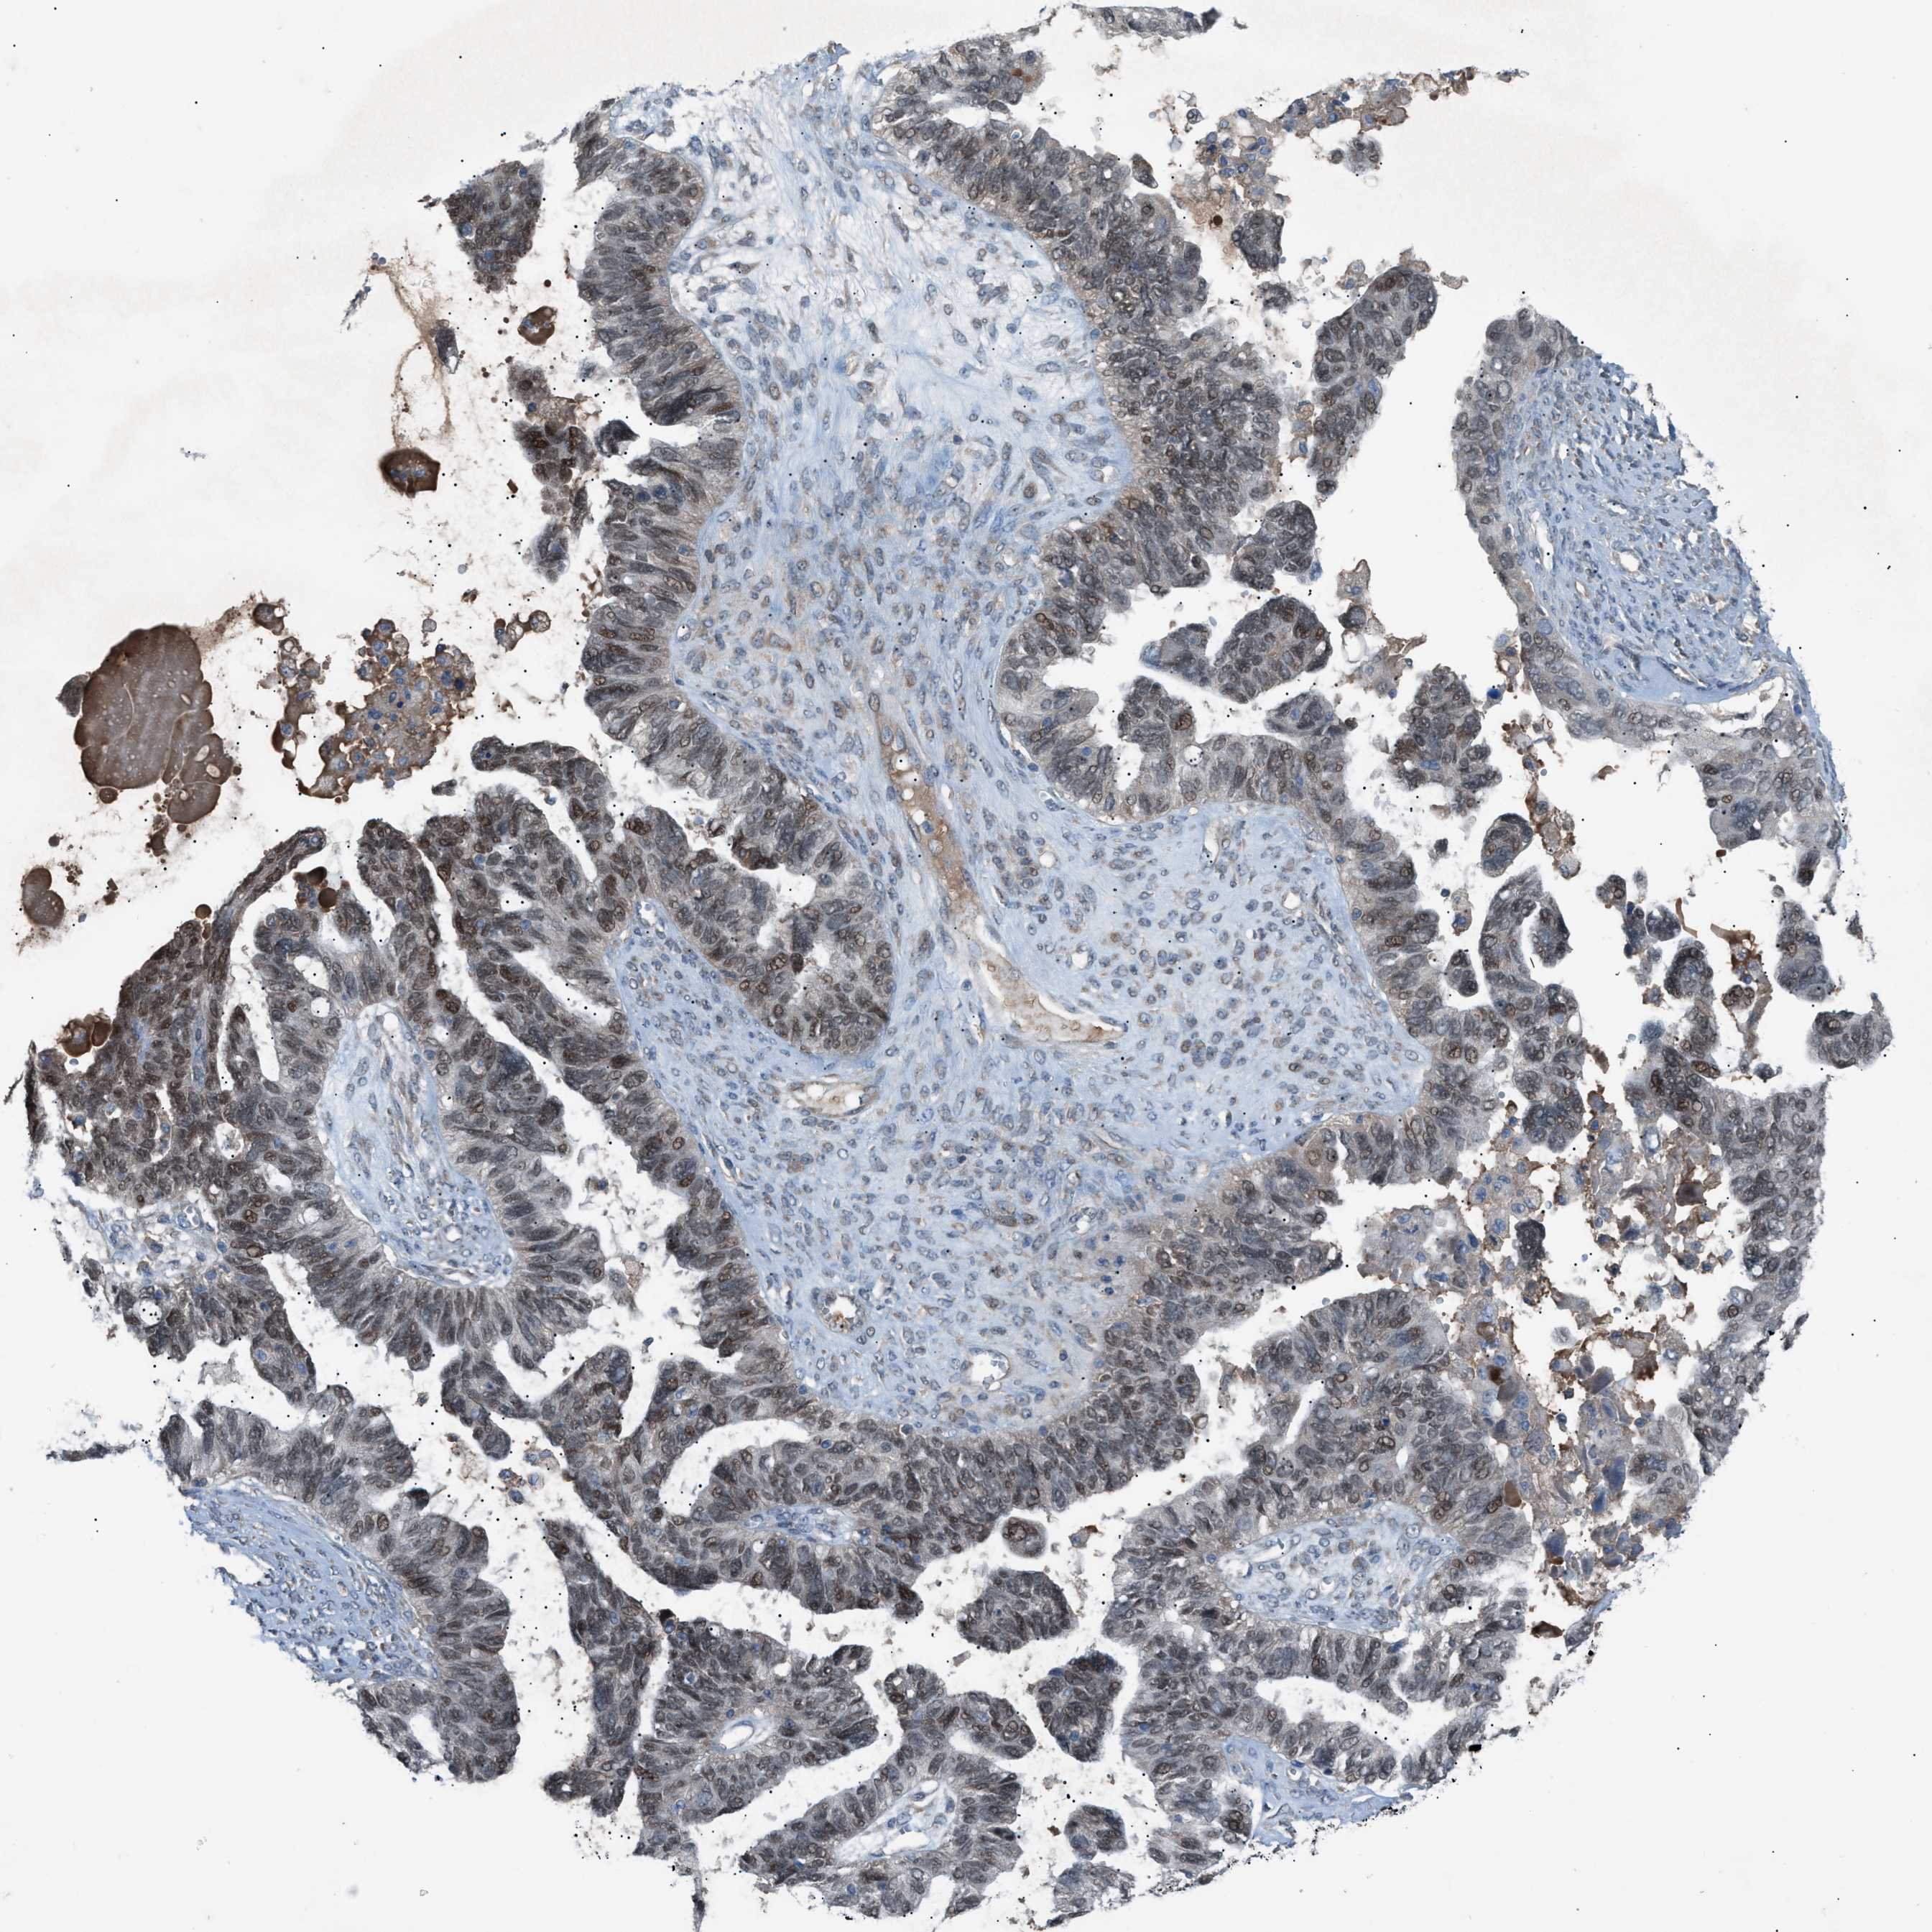

OVARIAN CANCER - Protein expressioni

A mouse-over function shows sample information and annotation data. Click on an image to view it in a full screen mode. Samples can be filtered based on level of antibody staining by selecting one or several of the following categories: high, medium, low and not detected. The assay and annotation is described here.

Note that samples used for immunohistochemistry by the Human Protein Atlas do not correspond to samples in the TCGA dataset.

Antibody stainingi

Antibody staining in the annotated cell types in the current human tissue is reported as not detected, low, medium, or high, based on conventional immunohistochemistry profiling in selected tissues. This score is based on the combination of the staining intensity and fraction of stained cells.

Each image is clickable and will lead to virtual microscopy that enables deeper exploration of all samples and also displays staining intensity scores, fraction scores and subcellular localization as well as patient and tissue information for each sample.

Antibody HPA015323

Antibody HPA015810

Carcinoma, endometroid

Cystadenocarcinoma, serous, NOS

Cystadenocarcinoma, mucinous, NOS

Carcinoma, NOS